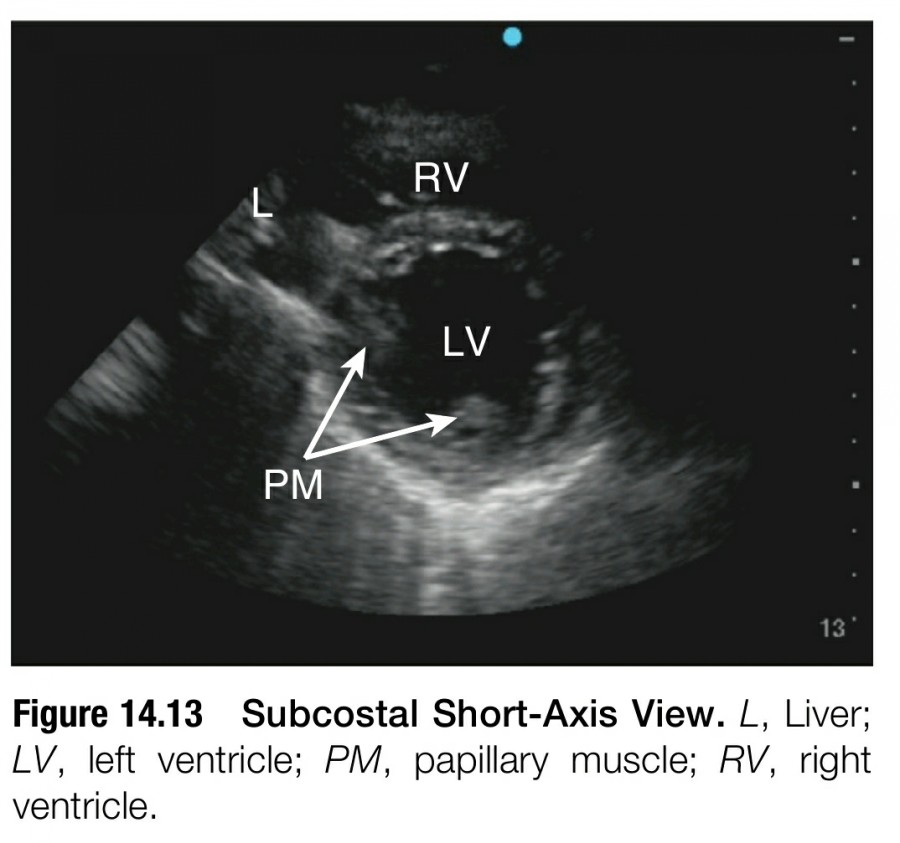

SUBCOSTAL SHORT-AXIS VIEW

Subcostal short-axis view는 prasternal short-axis view와 그 형태와 임상적인 유용성이 유사하다. Hemodynamic 평가를 확실하게 하기 위해서는 praternal window나 subcostal window에서 short-axis view를 확인해야 한다. Parasternal image quality가 떨어지는 obstructive lung disease patients나 mechanically ventilated patients에서는 subcostal short-axis view가 특히 유용하다.

Subcostal 4-chamber view에서 transducer를 반시계 방향으로 90' rotating 함으로써 transducer orientation marker가 환자의 머리 쪽으로 향하게 한다. Transducer를 rotating 할 때 처음 보이는 structure는 heart의 base인데, 이는 parasternal window에서 pulmonary artery level이나 AV level과 비슷하다. Papillary muscle level에서 midventicrular view를 보기 위해서 transducer가 cardiac apex를 향하도록 tilting 한다(figure 14.13).

Parasternal short-axis view와 비슷하게 subcostal short-axis view도 global LV systolic function과 segmental LV wall motion을 평가하는데 이용할 수 있다. Interventricular septal dynamics와 circumferential pericardial effusion의 확인 또한 가능하다.